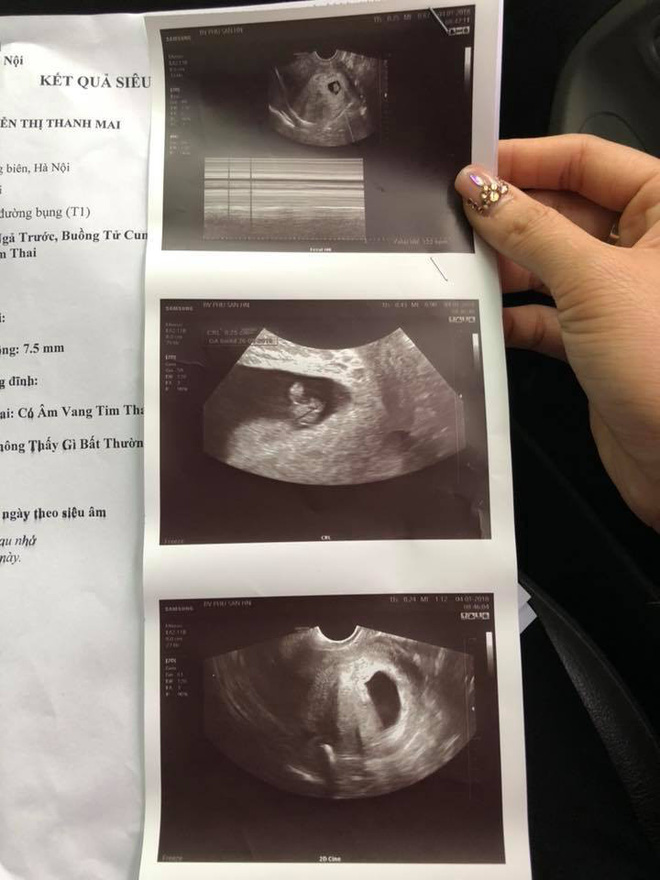

Kết quả siêu âm thai tại BV Sản HN |

"Sang bên đây tôi được đi siêu âm luôn và kết quả là tất cả các chỉ số thai bình thường, bác sĩ cho biết con tôi bình thường không bị làm sao. Bác sĩ cũng cho rằng đó chỉ là do tôi bị động thai, bác sĩ có nói thêm, thai bé như thế phải siêu âm đầu dò mới chuẩn đoán chính xác được. Sau đó, bác sĩ cho tôi đơn thuốc về nhà nghỉ ngơi điều trị tiêm cho thai ổn định.", thai phụ chia sẻ.